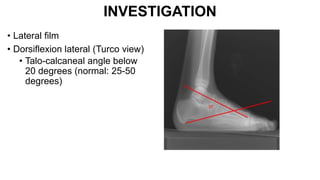

INVESTIGATION

• Lateral film

• Dorsiflexion lateral (Turco view)

• Talo-calcaneal angle below

20 degrees (normal: 25-50

degrees)